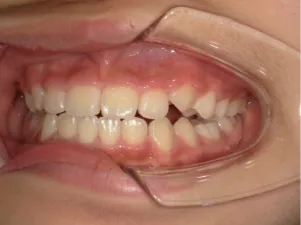

治療中➁小2(7y3m):成長期受け口用ファンクショナルアプライアンススタート

| 行ったご提案・診断内容 | 成長期に行う治療と咬合治療をご提案 受け口用ファンクショナルアプライアンス(写真②③)からスタートし、小2以降で上下顎の拡大・歯列弓の形態修正・前歯の並べ直し(写真④)を行いその後、モノブロック(筋機能的咬合誘導)装置(写真⑤)へ移行し、受け口の再発予防と永久歯を適切な咬み合わせに誘導し、必要によりマルチブラケット法へ移行する治療方法を提案しました。 成長期治療(成長時期にお口の環境を整える治療) 2年生以降から 咬合治療 |

| 治療期間 | 12か月:受け口用ファンクショナルアプライアンス(写真②③) 12カ月:成長期治療の動的治療期間(写真④) 現在、成長の経過観察と咬合誘導中です(写真⑤~⑨) |